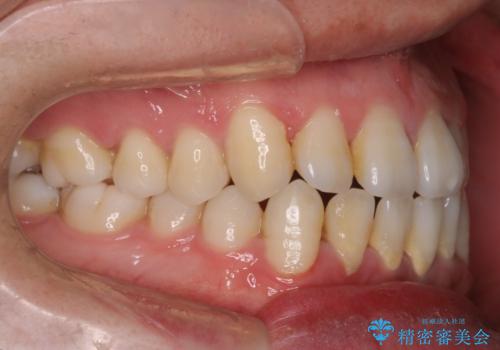

- 前歯のすきっ歯が気になると来院された患者様です。

前歯の隙間をマウスピース矯正(インビザライン)を使用して、閉じていきました。